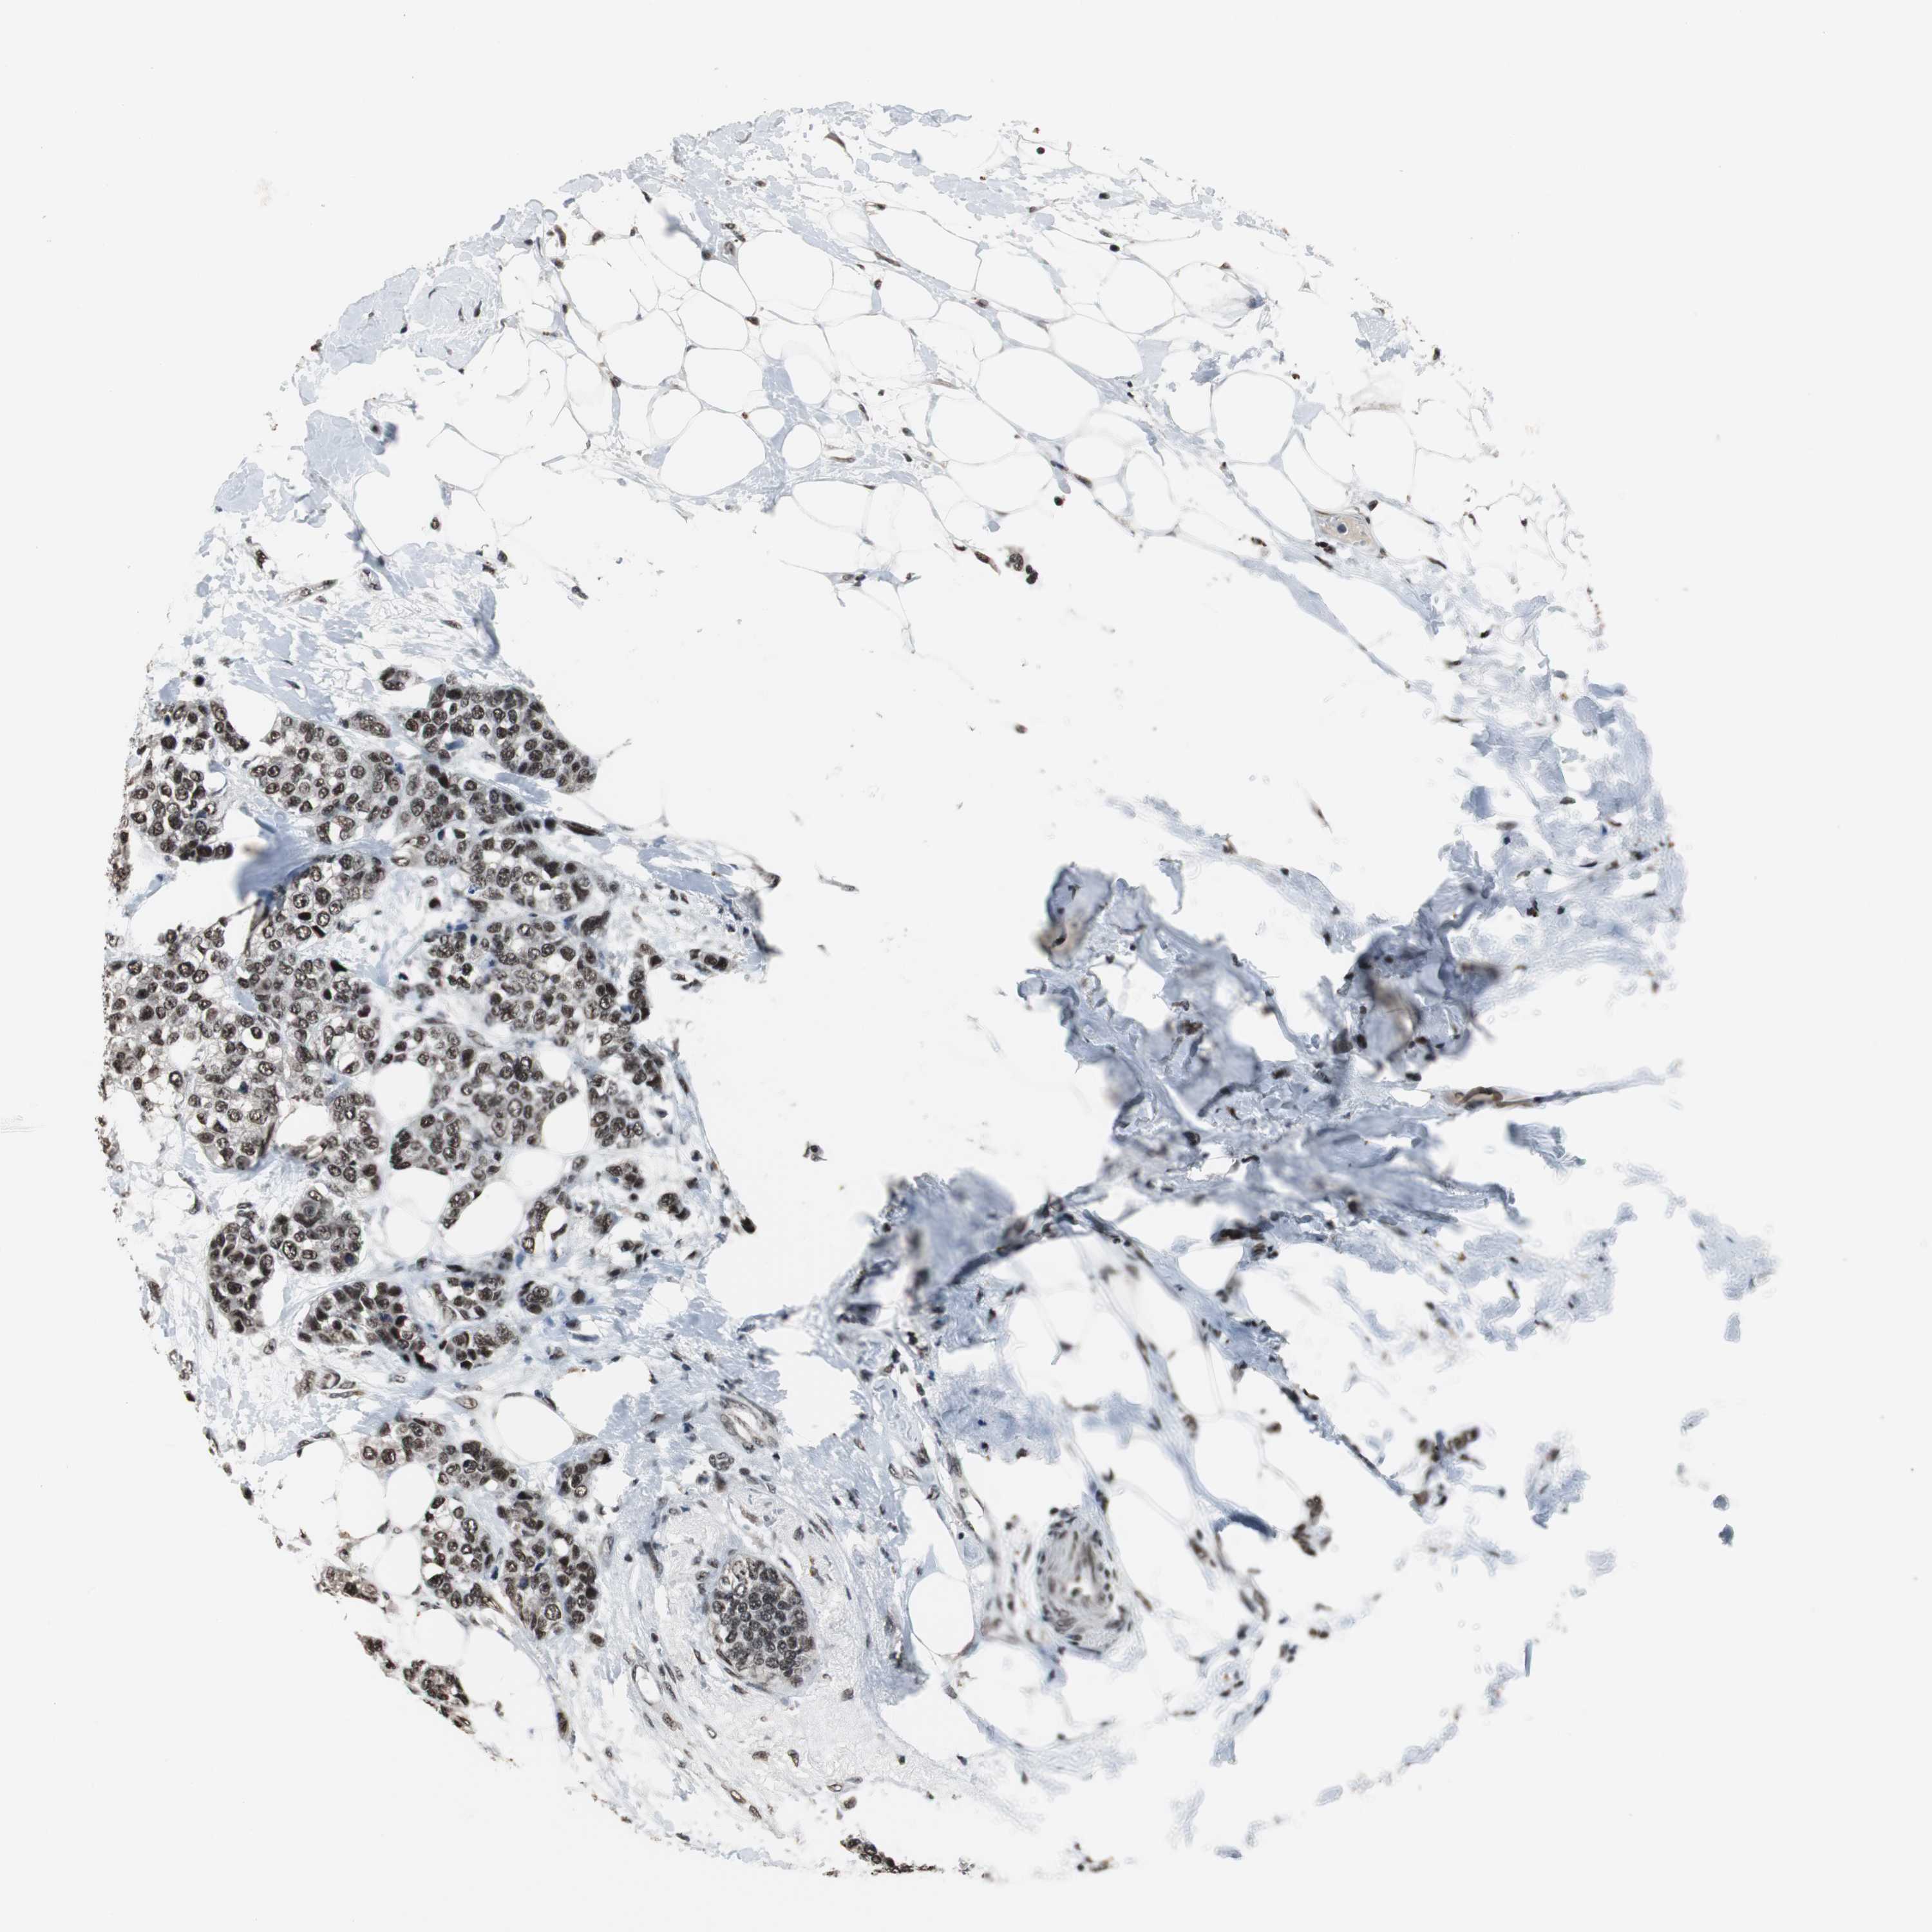

CANCER BREAST CANCER Show tissue menu

BRCA TCGA BRCA VALIDATION PROTEIN EXPRESSION